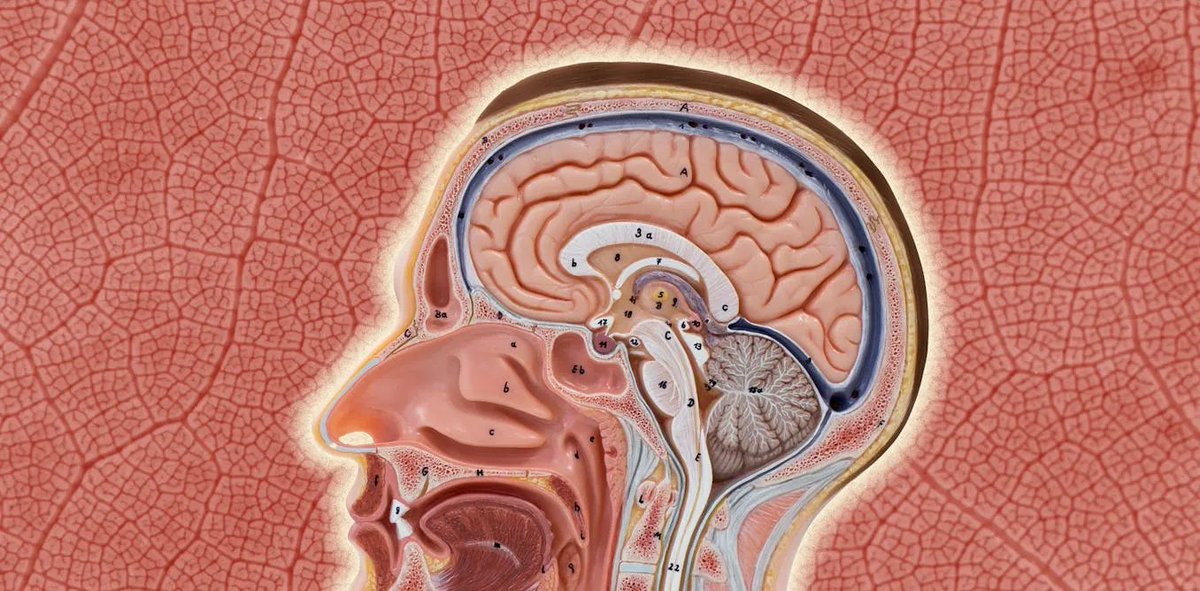

Persistent brain fog, memory issues, and mood volatility often share a common cause: blood-brain barrier breakdown.

Let's talk: Image The blood-brain barrier is only one cell thick. It's literally one microscopic layer of endothelial cells that stands between your brain and everything circulating in your blood.

When that layer fails, toxins, bacteria, inflammatory molecules, and metabolic waste products have full permission to cause havoc in your brain. The result isn't just brain fog or headaches. We're talking about the foundation for neurodegeneration, psychiatric disorders, and even chronic neuroinflammation.Image